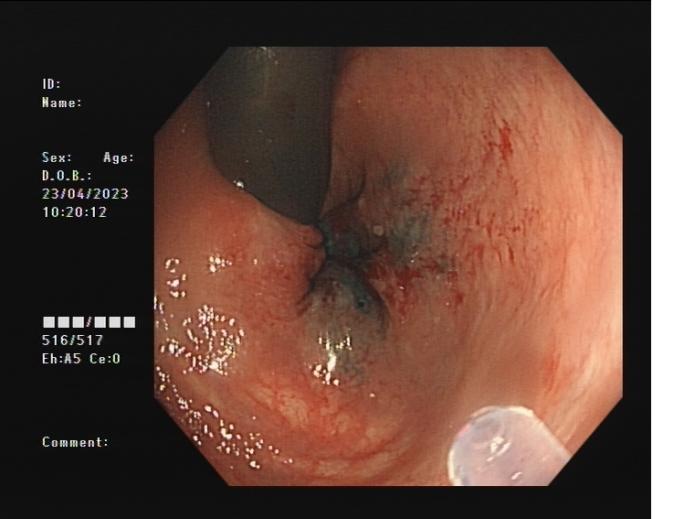

食管靜脈曲張 內鏡下套扎術

食管靜脈曲張套扎術(EVL):治療食管靜脈曲張、胃底靜脈曲張破裂出血、藥物止血無效者;既往有食管靜脈曲張破裂出血史者預防再出血。